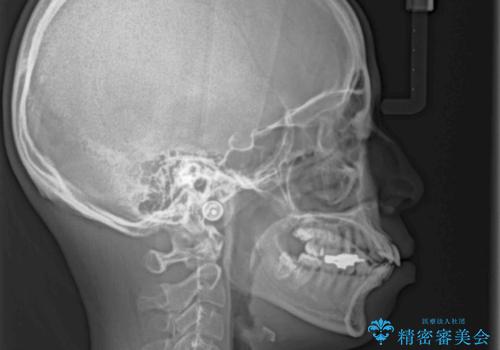

上下正中を左右対称に揃えるため、アンカースクリューや補助装置を使用しながら口元を下げていくこととしました。

積極的に前歯を牽引したことで、口元の閉じにくさは顕著に改善され、横顔のシルエットが大幅に変化しました。

口元を積極的に引っ込めるために、上下左右の小臼歯計4本を抜歯することとしました。

セオリーでは第一小臼歯を抜歯しますが、上下右側は第二小臼歯に銀歯が装着されているため、第二小臼歯を抜歯することとしました。